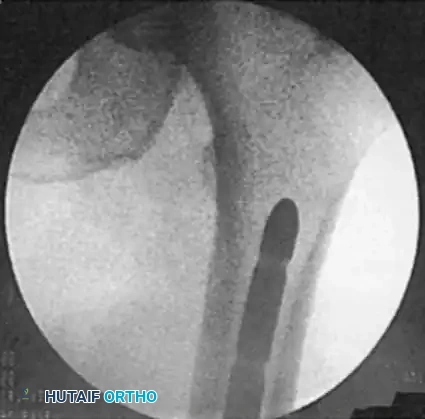

Proximal locking is performed freehand using the "perfect circle" technique.

1. Position the fluoroscope in the true AP plane at the level of the lesser trochanter. Adjust the C-arm until the locking hole in the nail appears as a perfect circle.

2. Make a longitudinal skin incision over the lateral thigh at this level. Sharply divide the fascia lata and bluntly dissect the vastus lateralis to the bone.

3. Using a radiolucent drill drive, align the drill tip precisely in the center of the perfect circle. Drill through the lateral cortex, pass through the nail hole, and penetrate the medial cortex.

4. Measure the depth and place the interlocking screw using a captured screwdriver.